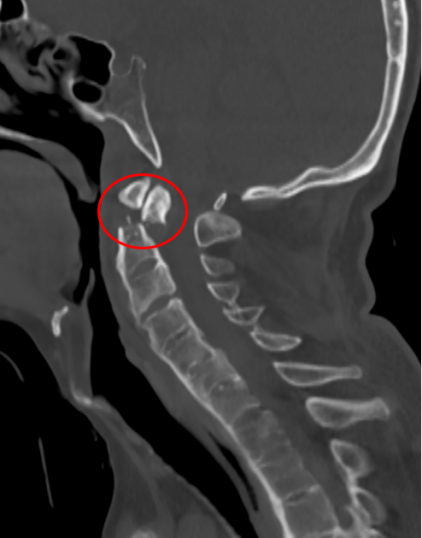

去年,家住昆山的金先生走路的时候不慎摔倒,下颌撞击硬物后感到颈部疼痛难忍,到当地医院查CT显示:(枢椎)齿状突骨折,骨折块向椎管方向移位。齿状突骨折属于上颈椎,位于头颅和颈椎的交界区域,是连接生命中枢的要塞,解剖结构复杂,有椎动脉和中枢神经从中穿过,稍有不慎就会引起大出血、瘫痪、甚至立即死亡。这类手术属于上颈椎手术,曾一度被视为骨科的手术禁区,国内仅有少数医院能够开展这一类手术,一般医师不敢轻易尝试。在业内医师的推荐下,家属送金先生来到了苏州大学附属独墅湖医院,找到了姜为民主任。

金先生伤后第7天,姜主任医师团队在麻醉手术科的密切配合下成功为他实施手术。姜主任凭借多年徒手置钉的过硬技术经验,2小时不到便完成了手术,术中出血仅100ml。术后CT显示齿状突完美复位,螺钉“不偏不倚”的位置恰到好处。术后,金先生在骨科护士长张霞芬护理团队的精心护理下,15天后伤口拆线康复出院。